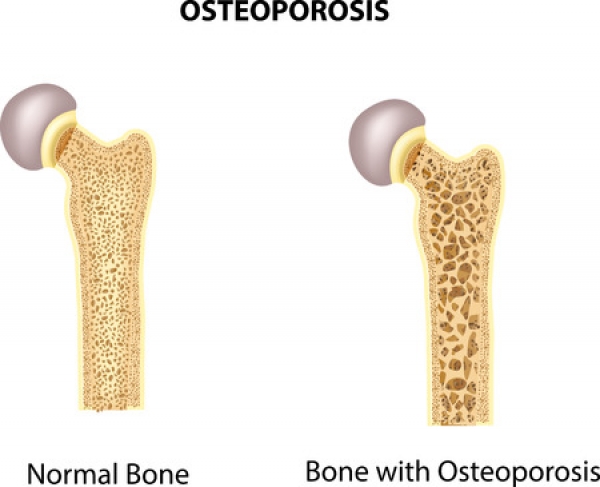

Osteoporosis causes a bone fracture in one out of every two women and one out of every four men over the age of 50. Since May is National Osteoporosis Month, we at Superior Foot & Ankle Care Center think this is a good time to talk about this disease, which can have a big impact on the health of your feet.

Osteoporosis occurs when you lose too much bone, make too little bone or both. Many patients don’t realize that bone is living tissue that is constantly being torn down and built up. There are many conditions and factors that can result in loss of bone strength. These include:

- Age—your risk increases over the age of 50

- Sex—women have a higher risk, particularly post-menopausal women

- Ethnicity—Latinos, Asian Americans and African Americans are more at risk

- Disease—osteoporosis is often associated with other disease, such as diabetes, lupus and rheumatoid arthritis

- Family history of osteoporosis

If you are experiencing symptoms such as pain, tenderness, swelling, bruising or difficulty bearing weight on the affected foot, it’s important that you not put off getting these symptoms evaluated. Make an appointment at our Long Beach office so that our podiatrists, Dr. Victoria M. Foley or Dr. Constance Ornelas can examine your foot and diagnose the problem and its cause. The foot doctor can help determine your personal risk for osteoporosis and whether or not bone density or other tests should be ordered at this time.

Making Choices for Healthy Bones

Fortunately, there are many ways you can help increase bone strength and lower your risk for fractures, such as:

- Get enough calcium—know how much you should be getting each day and increase your intake of s of yogurt, milk, cheese, leafy greens and other foods that are high in this nutrient. Be sure to also get adequate amounts of vitamin D as this is essential for body to absorb calcium properly.

- Exercise regularly—weight-bearing and muscle strengthening build stronger bones. In general, being active can reduce your risk for decreased bone strength.

- Don’t smoke.

- Fall-proof your home inside and out.

Being educated is your best defense against osteoporosis. Have more questions? Contact us at: (562) 420-9800.